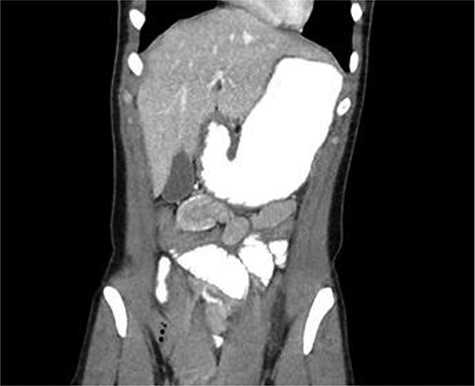

CT scan diagnosed 100% of the cases and all cases were reported as jejunojejunal (JJ) intussusception (Figs 1, 2). CT scan identified two patients having more than one intussuscepted segment. None of the patients were found to have lead points on imaging.

A 30-year-old male with CT scan with target sign in left upper quadrant suggesting JJ intussusception